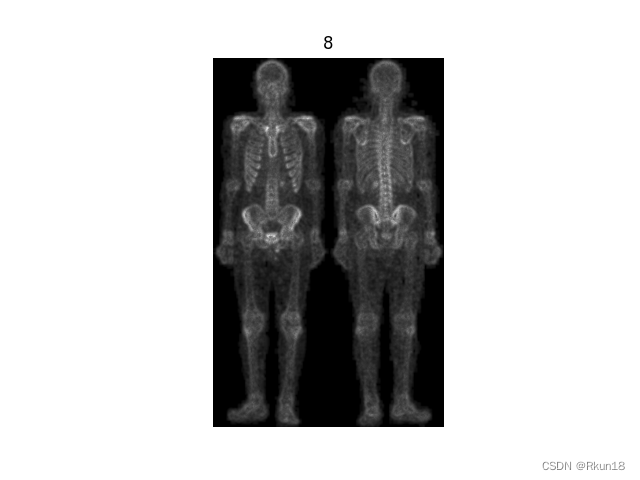

8:对7进行灰度幂律变换得到最终结果:

图8进行幂律变换后增大了一些噪声,但同时人体结构更加清晰完整,人体轮廓清晰度也有一定提高。